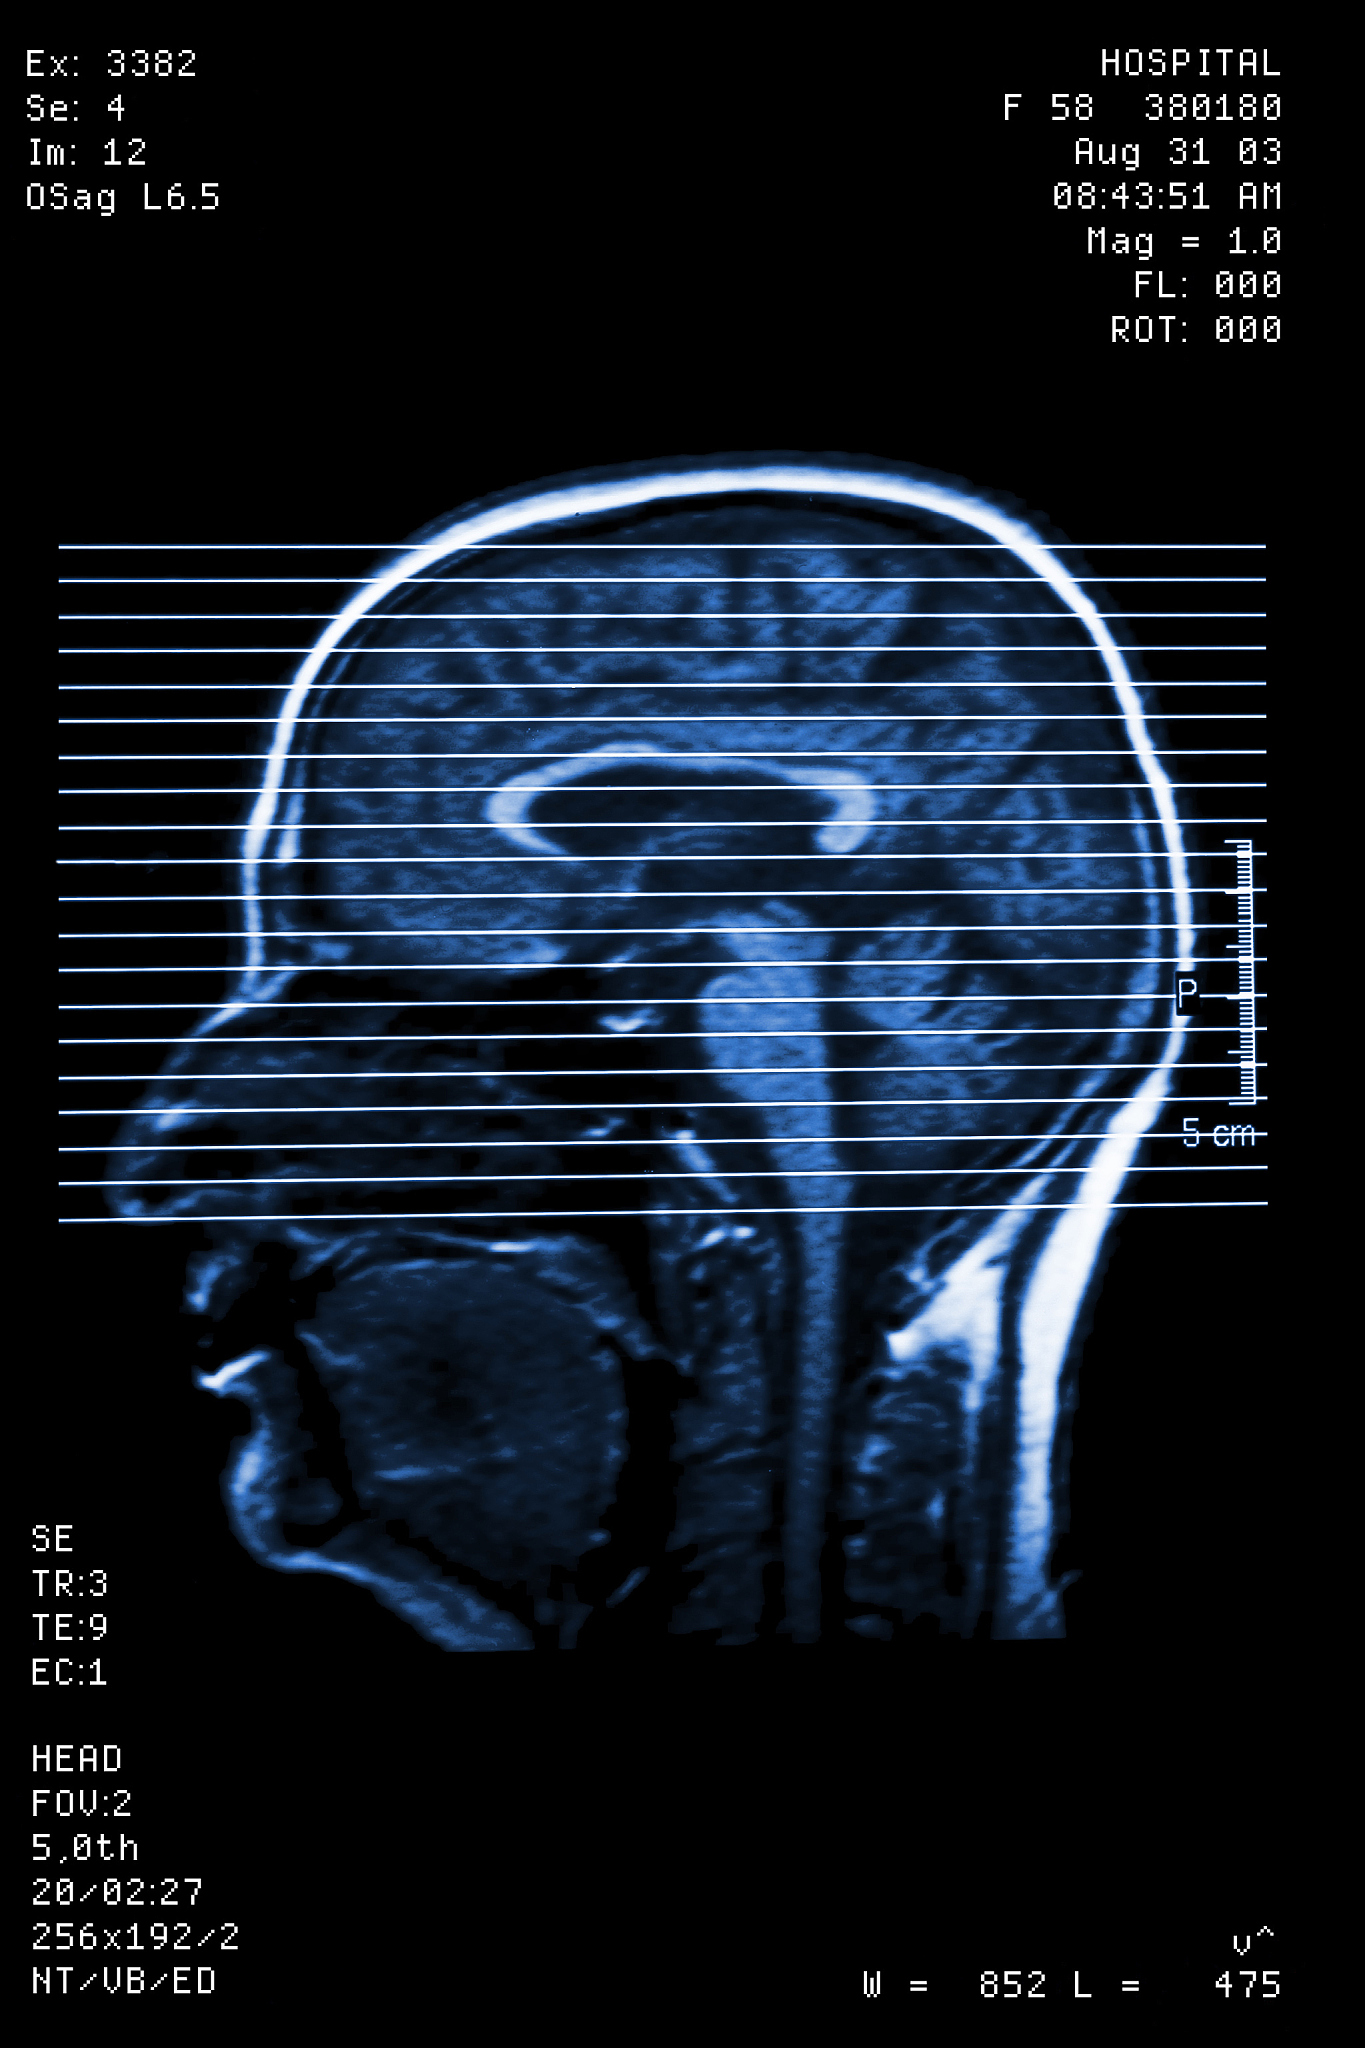

下午,我参加了一个关于神经外科手术的讲座。讲座让我更加了解神经外科手术的过程和注意事项。这使我更加自信,可以更好地照顾病人。